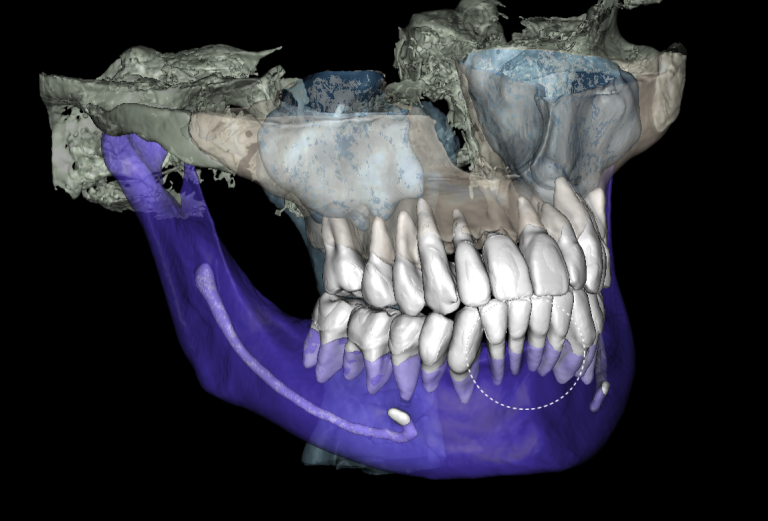

3D reconstruction created on the basis of DICOM and an intraoral scan in the Diagnocat STL module allows you to choose the optimal size and location of the implants

A template for guided implant surgery was planned and manufactured based on these digital models for the replacement of teeth 24 (Universal 12) and 25 (Universal 13)

Based on digital models, a virtual design of a template has been planned for the replacement of tooth 36 (Universal 19)